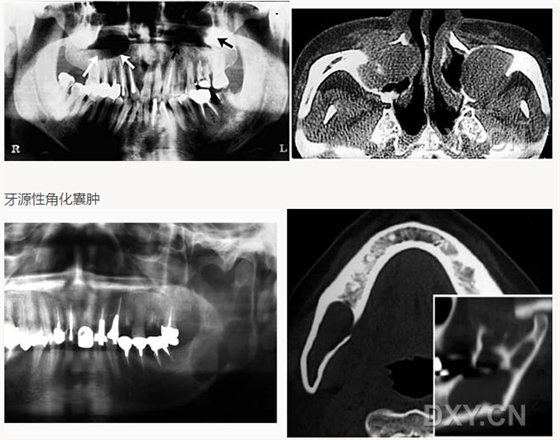

牙源性角化囊腫

牙源性鈣化囊腫

牙瘤!

牙源性鈣化囊腫    牙瘤!